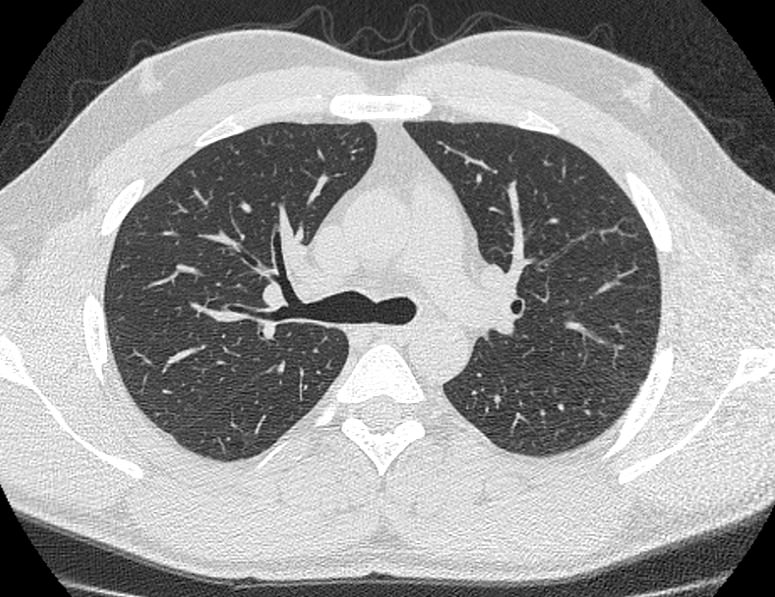

В нашей клинике КТ бронхов проводится на новейшем 128-срезовом мультиспиральном компьютерном томографе экспертного класса TOSHIBA AQUILION CXL. Аппарат оснащен увеличенным количеством сверхчувствительных детекторов, которые позволяют проводить тончайшие срезы анатомической области с толщиной от 0,5 мм за несколько секунд. Быстрое выполнение процедуры обеспечивает минимальный уровень рентгеновского облучения, при этом исследование выполняется без применения контрастирования.

На основе данных, полученных при сканировании, аппарат создает наглядную 3D модель бронхиального дерева с высочайшей точностью и достоверностью, которая позволяет просматривать интересующие анатомические структуры в разных плоскостях. Метод обладает высокой точностью и дает возможность исследовать мелкие бронхи и бронхиолы, которые из-за узкого просвета бывает невозможно осмотреть при помощи эндоскопической бронхоскопии (возможности метода ограничены размером зонда).